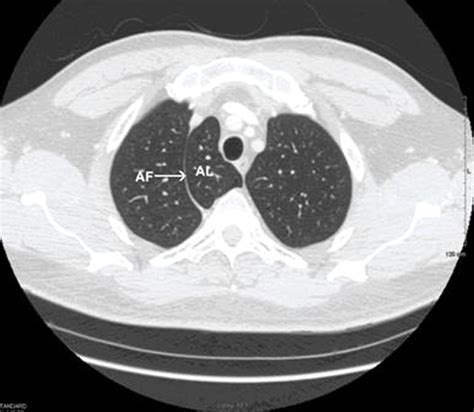

• The Azygos Fissure Line: A thin, convex line extending from the apex of the right lung toward the hilum.

• The Azygos Point (or Teardrop): A dense, teardrop-shaped opacity at the inferior end of the fissure line. This represents the cross-section of the misplaced azygos vein itself.

While standard chest X-rays are usually sufficient for diagnosis, computed tomography (CT) provides a definitive view. On a CT scan, the Vena Azygos Lobe is clearly demonstrated as an isolated pleural-lined segment of lung tissue separated from the rest of the right upper lobe by the azygos fissure.